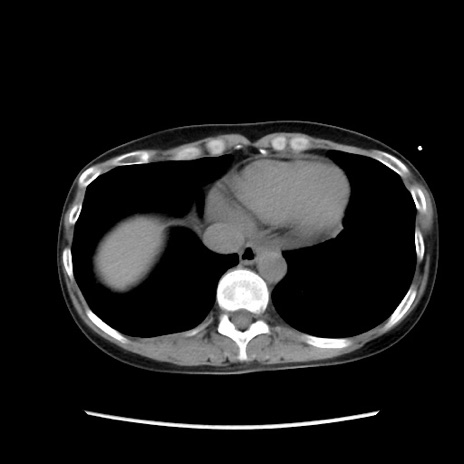

症例32(横断像)

【症例】40歳代 女性

【主訴】上腹部痛、嘔気・嘔吐

【現病歴】約9時間前頃から急に上腹部痛、嘔気、嘔吐が出現。改善しないため救急要請。

【既往歴】子宮頚癌(広汎子宮全摘術、放射線療法)、腸閉塞

【身体所見】腹部:平坦、軟、腸雑音亢進、上腹部を中心に腹部全体に圧痛あり。

【データ】WBC 8400、CRP 0.03